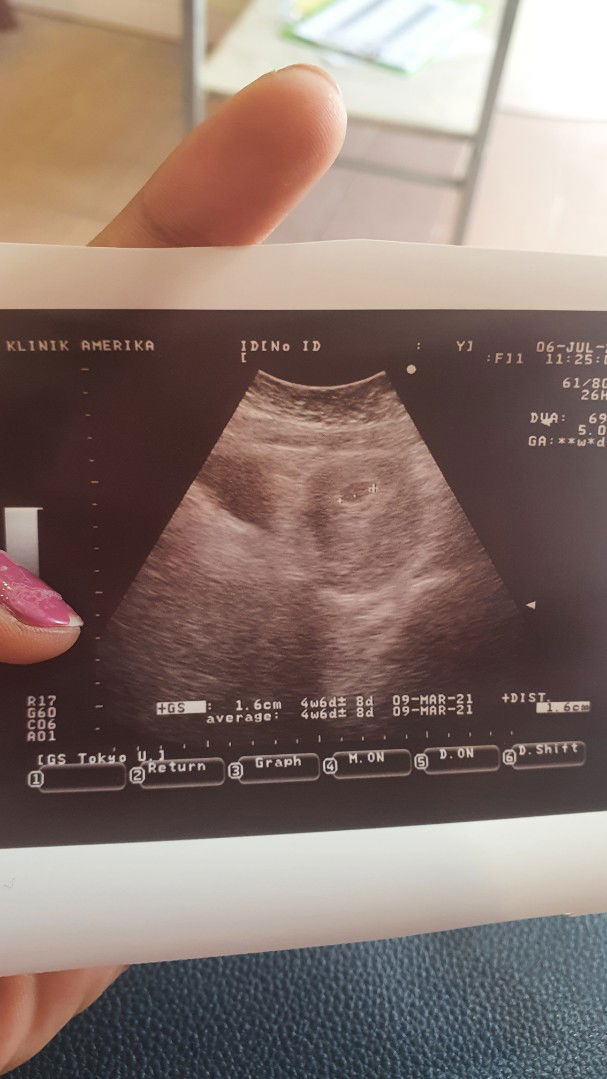

06.07.2020# Ikut app dah 7 weeks 1 day.. xdi pegi scan dr cakap baby kecil.. baru 4 weeks 6 days.. worried plk.. ade mommies pengalaman macam ni πŸ˜”

Scan dengan last date period x sama